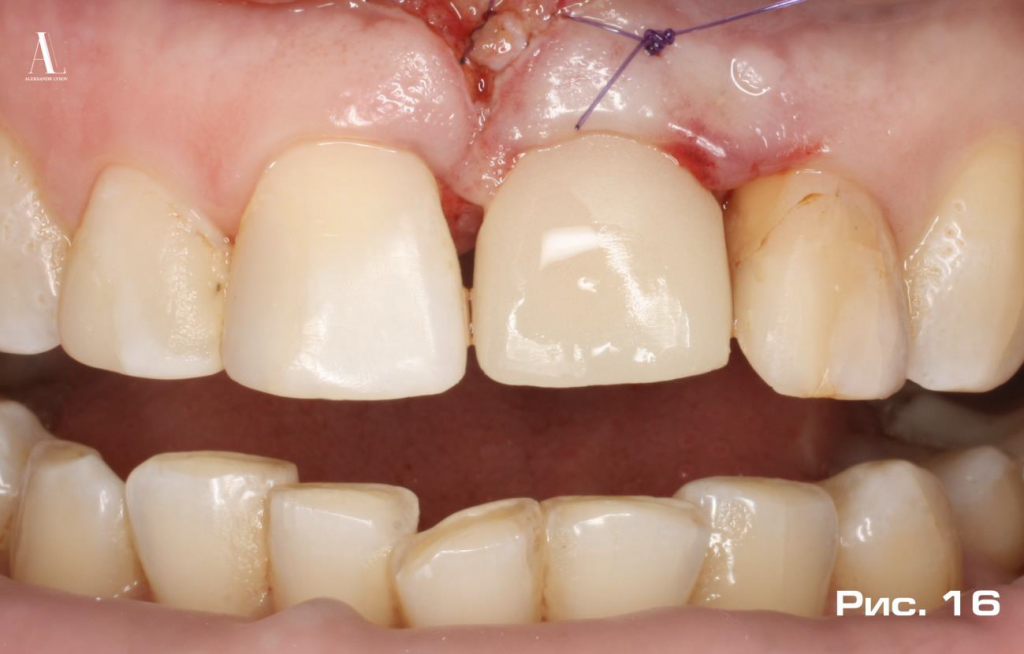

С целью иммобилизации мягких тканей, в зоне оперативного вмешательства, провели френулоплатику уздечки верхней губы. Временную коронку зафиксировали на небольшое количество временного цемента (Рис. 16).